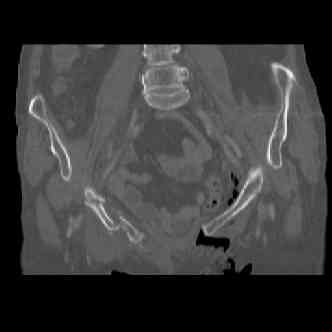

attached are images of a 70 year old female after peds versus car. her own car ran her over.

injuries are limited to the pelvis. left rami open and visible in a 10cm vertical laceration just lateral to left labia majora. wound is grossly clean. no vaginal and no urinary issues. CT scan shows widening of both SI joints anteriorly but I think this is vertically stable pattern.

attached are several CT cuts. please let me know if you need more. the CT is pre-pelvic ex-fix placement.